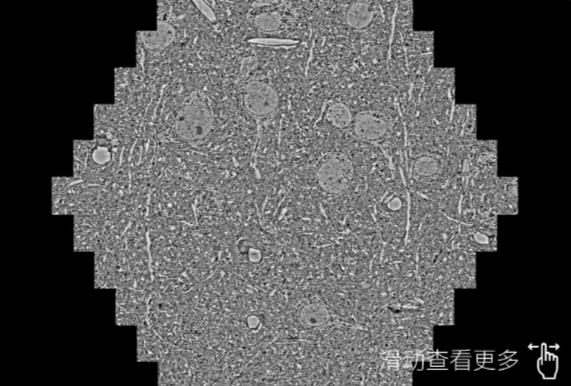

鼠脑切片。左图使用大同蔡司大同扫描电镜MultiSEM706对165μmx143pm面积区域成像,耗时仅需1.5秒。右图为鼠脑切片中30μm区域放大效果。样品由芝加哥大学B.Kasthuri提供。

使用蔡司高速大同扫描电镜MultiSEM对1mm²人脑皮层组织进行高分辨成像,并对其中的各种细胞结构进行三维重构分析。左图展示了2x3mm²组织平面中锥体神经元的三维重构效果。右图显示了局部体积神经元三维重构。图像由哈佛大学chtman实验室提供,渲染图由D. Berger 制作。